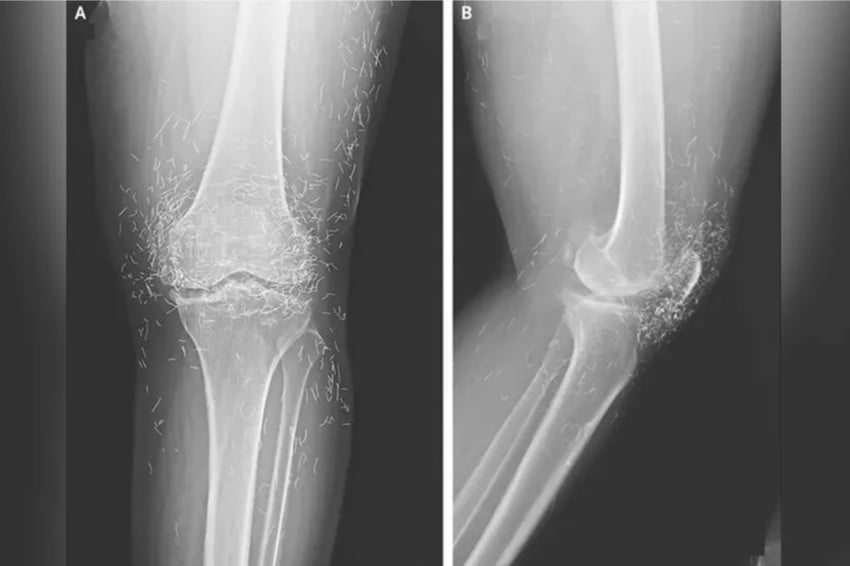

Sebuah peristiwa medis yang mengejutkan terjadi di Korea Selatan ketika tim dokter menemukan ratusan benang emas murni yang tertanam di lutut seorang pasien. Foto/Oddity Central

Dilansir dari Oddity Central, Jumat (19/9/2025), temuan ini sontak menjadi perhatian publik karena mengungkap praktik pengobatan alternatif yang tidak lazim namun masih populer di beberapa negara Asia.

Penemuan Mengejutkan di Korea Selatan